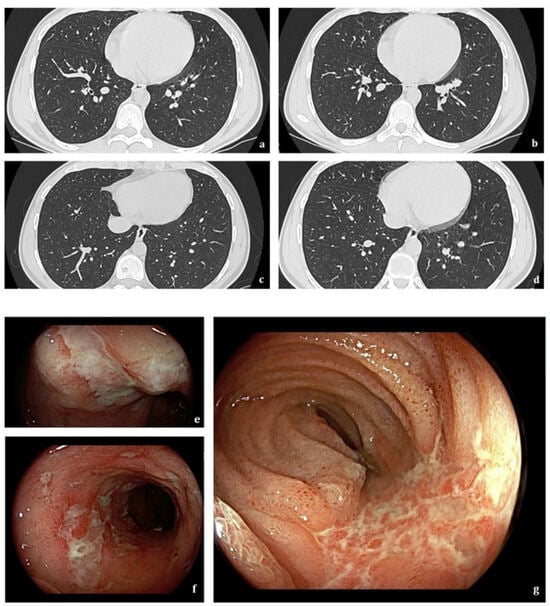

- Lissner, D.; Glauben, R.; Allers, K.; Sonnenberg, E.; Loddenkemper, C.; Schneider, T.; Siegmund, B. Pulmonary Manifestation of Crohn’s Disease Developed Under Treatment with Vedolizumab. Am. J. Gastroenterol. 2018, 113, 146–148. [Google Scholar] [CrossRef]

- Abu Shtaya, A.; Cohen, S.; Kogan, Y.; Shteinberg, M.; Sagol, O. Crohn’s Disease with Atypical Extra-Intestinal Manifestations Developing Under Treatment with Vedolizumab. Eur. J. Case Rep. Intern. Med. 2021, 8, 002265. [Google Scholar] [CrossRef] [PubMed]

- Myc, L.A.; Girton, M.R.; Stoler, M.H.; Davis, E.M. Necrobiotic Pulmonary Nodules of Crohn’s Disease in a Patient Receiving Vedolizumab. Am. J. Respir. Crit. Care Med. 2019, 199, e1–e2. [Google Scholar] [CrossRef] [PubMed]